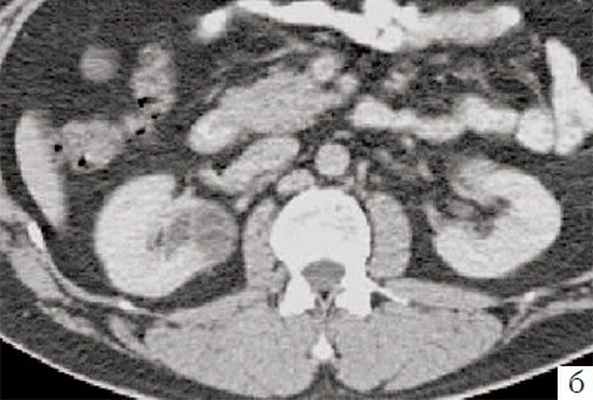

(Слева) КТ с контрастированием, аксиальная проекция: классическая мультилокулярная кистозная нефрома в виде кистозного образования со множеством перегородок, выступающего в почечный синус. Почка функционирует нормально, отсутствуют васкулярная инвазия, лимфаденопатия и другие признаки злокачественности.

(Справа) КТ с контрастированием, аксиальная проекция: у этого же пациента выявлена классическая мультилокулярная кистозная нефрома в виде инкапсулированного поликистозного образования, выступающего в почечный синус.